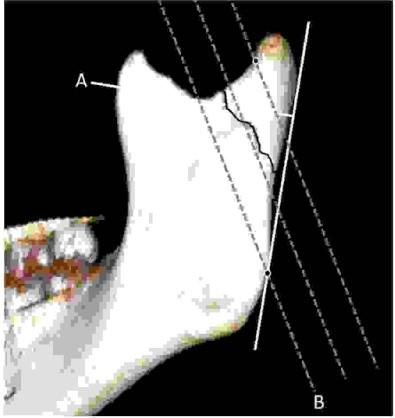

Klasyfikacja złamań wyrostka kłykciowego żuchwy oparta na liniach referencyjnych o przebiegu skośnym (klasyfikacja Kozakiewicza):

Widoczne złamanie wg klasyfikacji Kozakiewicza to: